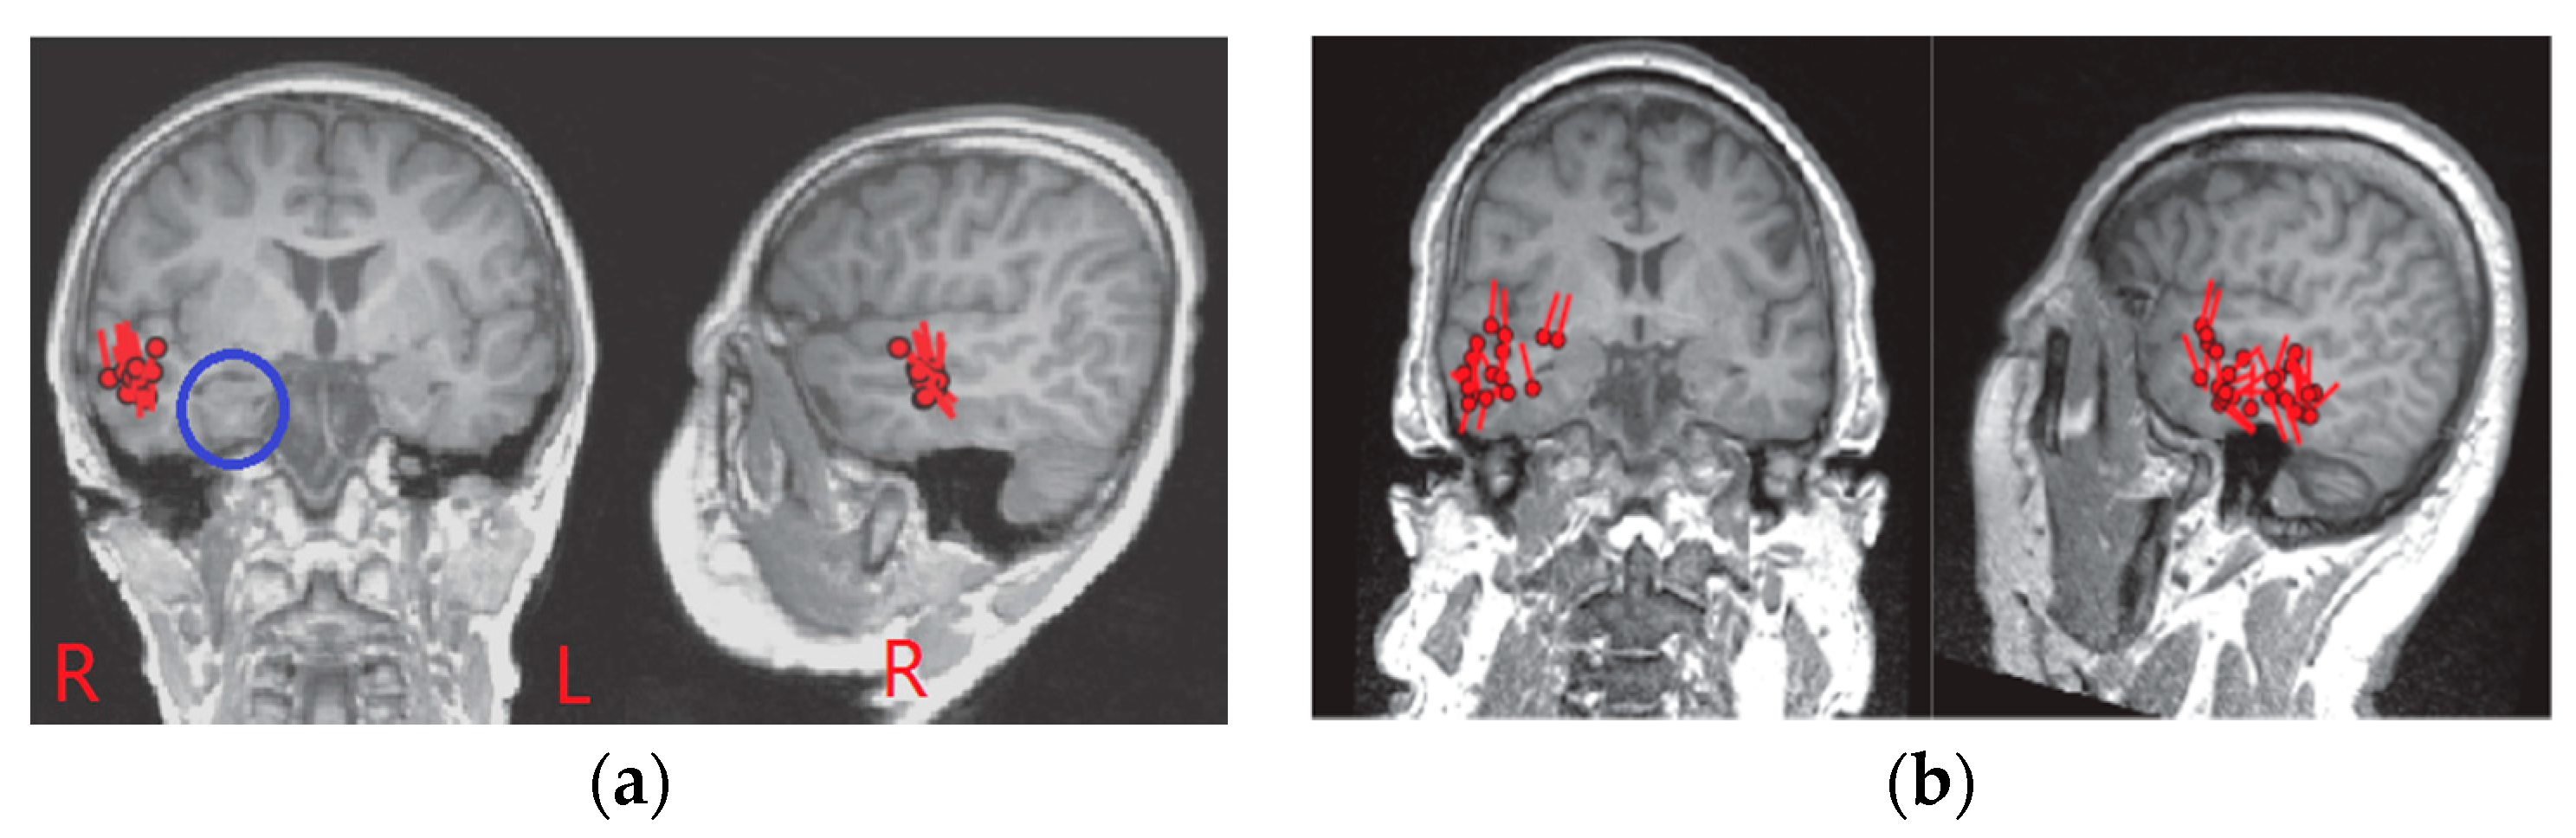

3.3. Epileptogenic Zone Localization Results